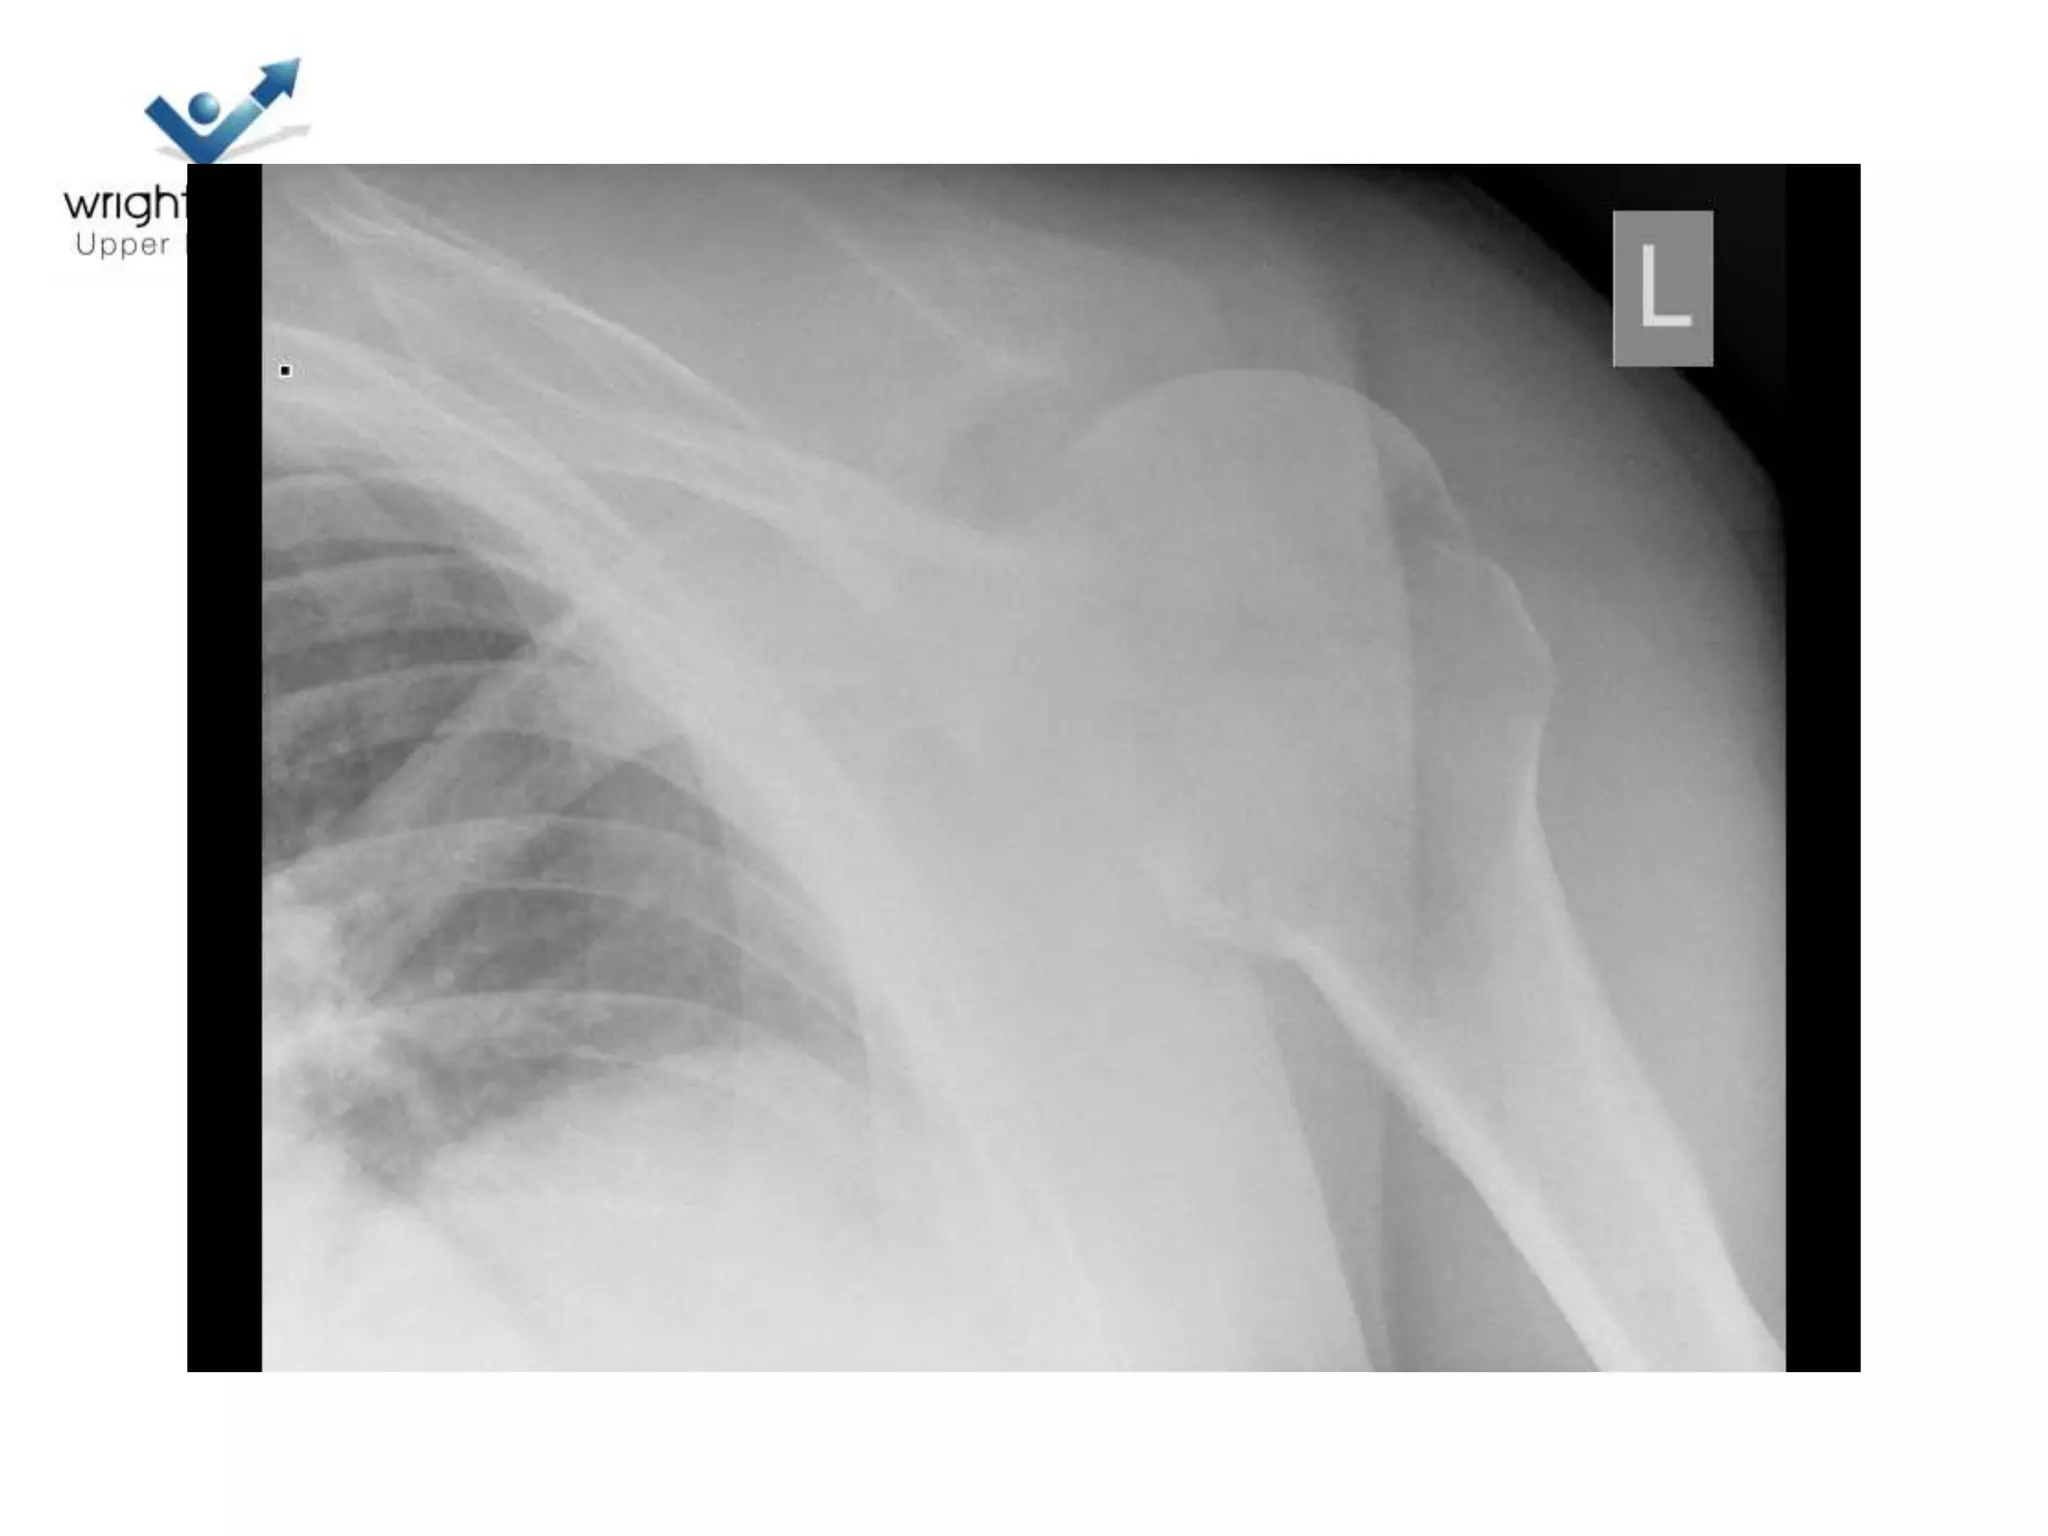

Case discussions

3 Next